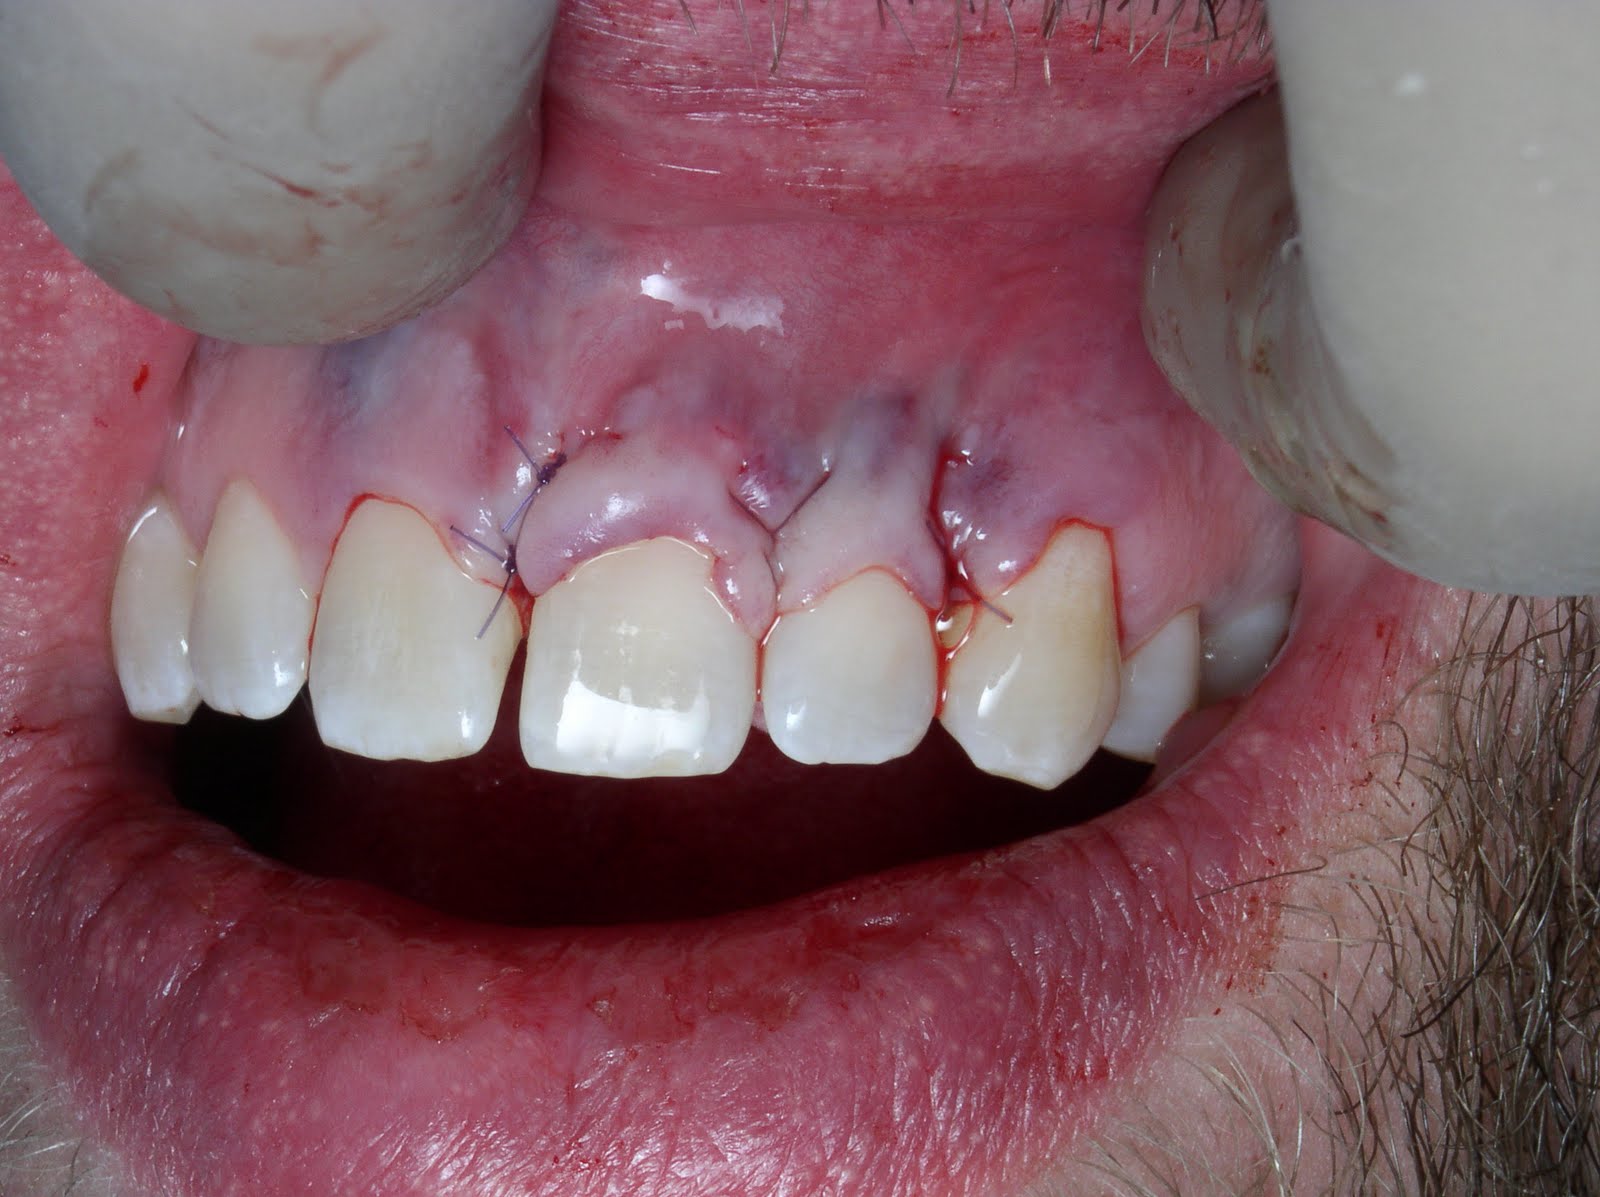

JCM Free FullText SoftTissue Augmentation around Dental Implants

Anterior dental Bridge Connective tissue grafts for better aesthetics Dental Code For Connective Tissue Graft this dental procedure code refers to the type of grafting that takes tissue from within the mouth to cover teeth with receding gums. the ada code d4273: according to weinberg et al., when focusing on an isolated tooth or multiple adjacent teeth and aiming for root coverage, a subepithelial. this guide addresses coding for graft scenarios. Dental Code For Connective Tissue Graft.

JCM Free FullText SoftTissue Augmentation around Dental Implants Dental Code For Connective Tissue Graft this guide addresses coding for graft scenarios where the collection and placement procedures are documented. this dental procedure code refers to the type of grafting that takes tissue from within the mouth to cover teeth with receding gums. according to weinberg et al., when focusing on an isolated tooth or multiple adjacent teeth and aiming for root. Dental Code For Connective Tissue Graft.